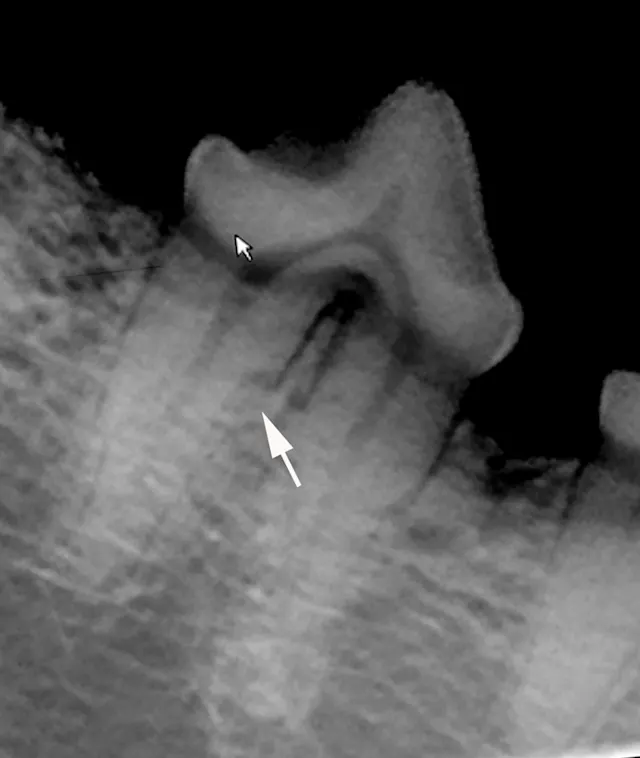

FIGURE 1A

Intraoral radiograph of the left mandibular fourth premolar; the distal root is affected by external resorption that has not extended into the oral cavity.

1. Recheck

When resorption begins deep in the alveolus on the root surface, the periodontal ligament and root parts may be replaced with bone- or cementum-like tissue via a noninflammatory process. If the lesion does not appear to extend into the oral cavity, it can be monitored for progression q6mo. Watchful waiting is indicated in cases with minimal root involvement not extending into the oral cavity; follow-up intraoral radiography q6–12mo is recommended accordingly. If the resorption area approaches or extends into the oral cavity, extraction is the treatment of choice.